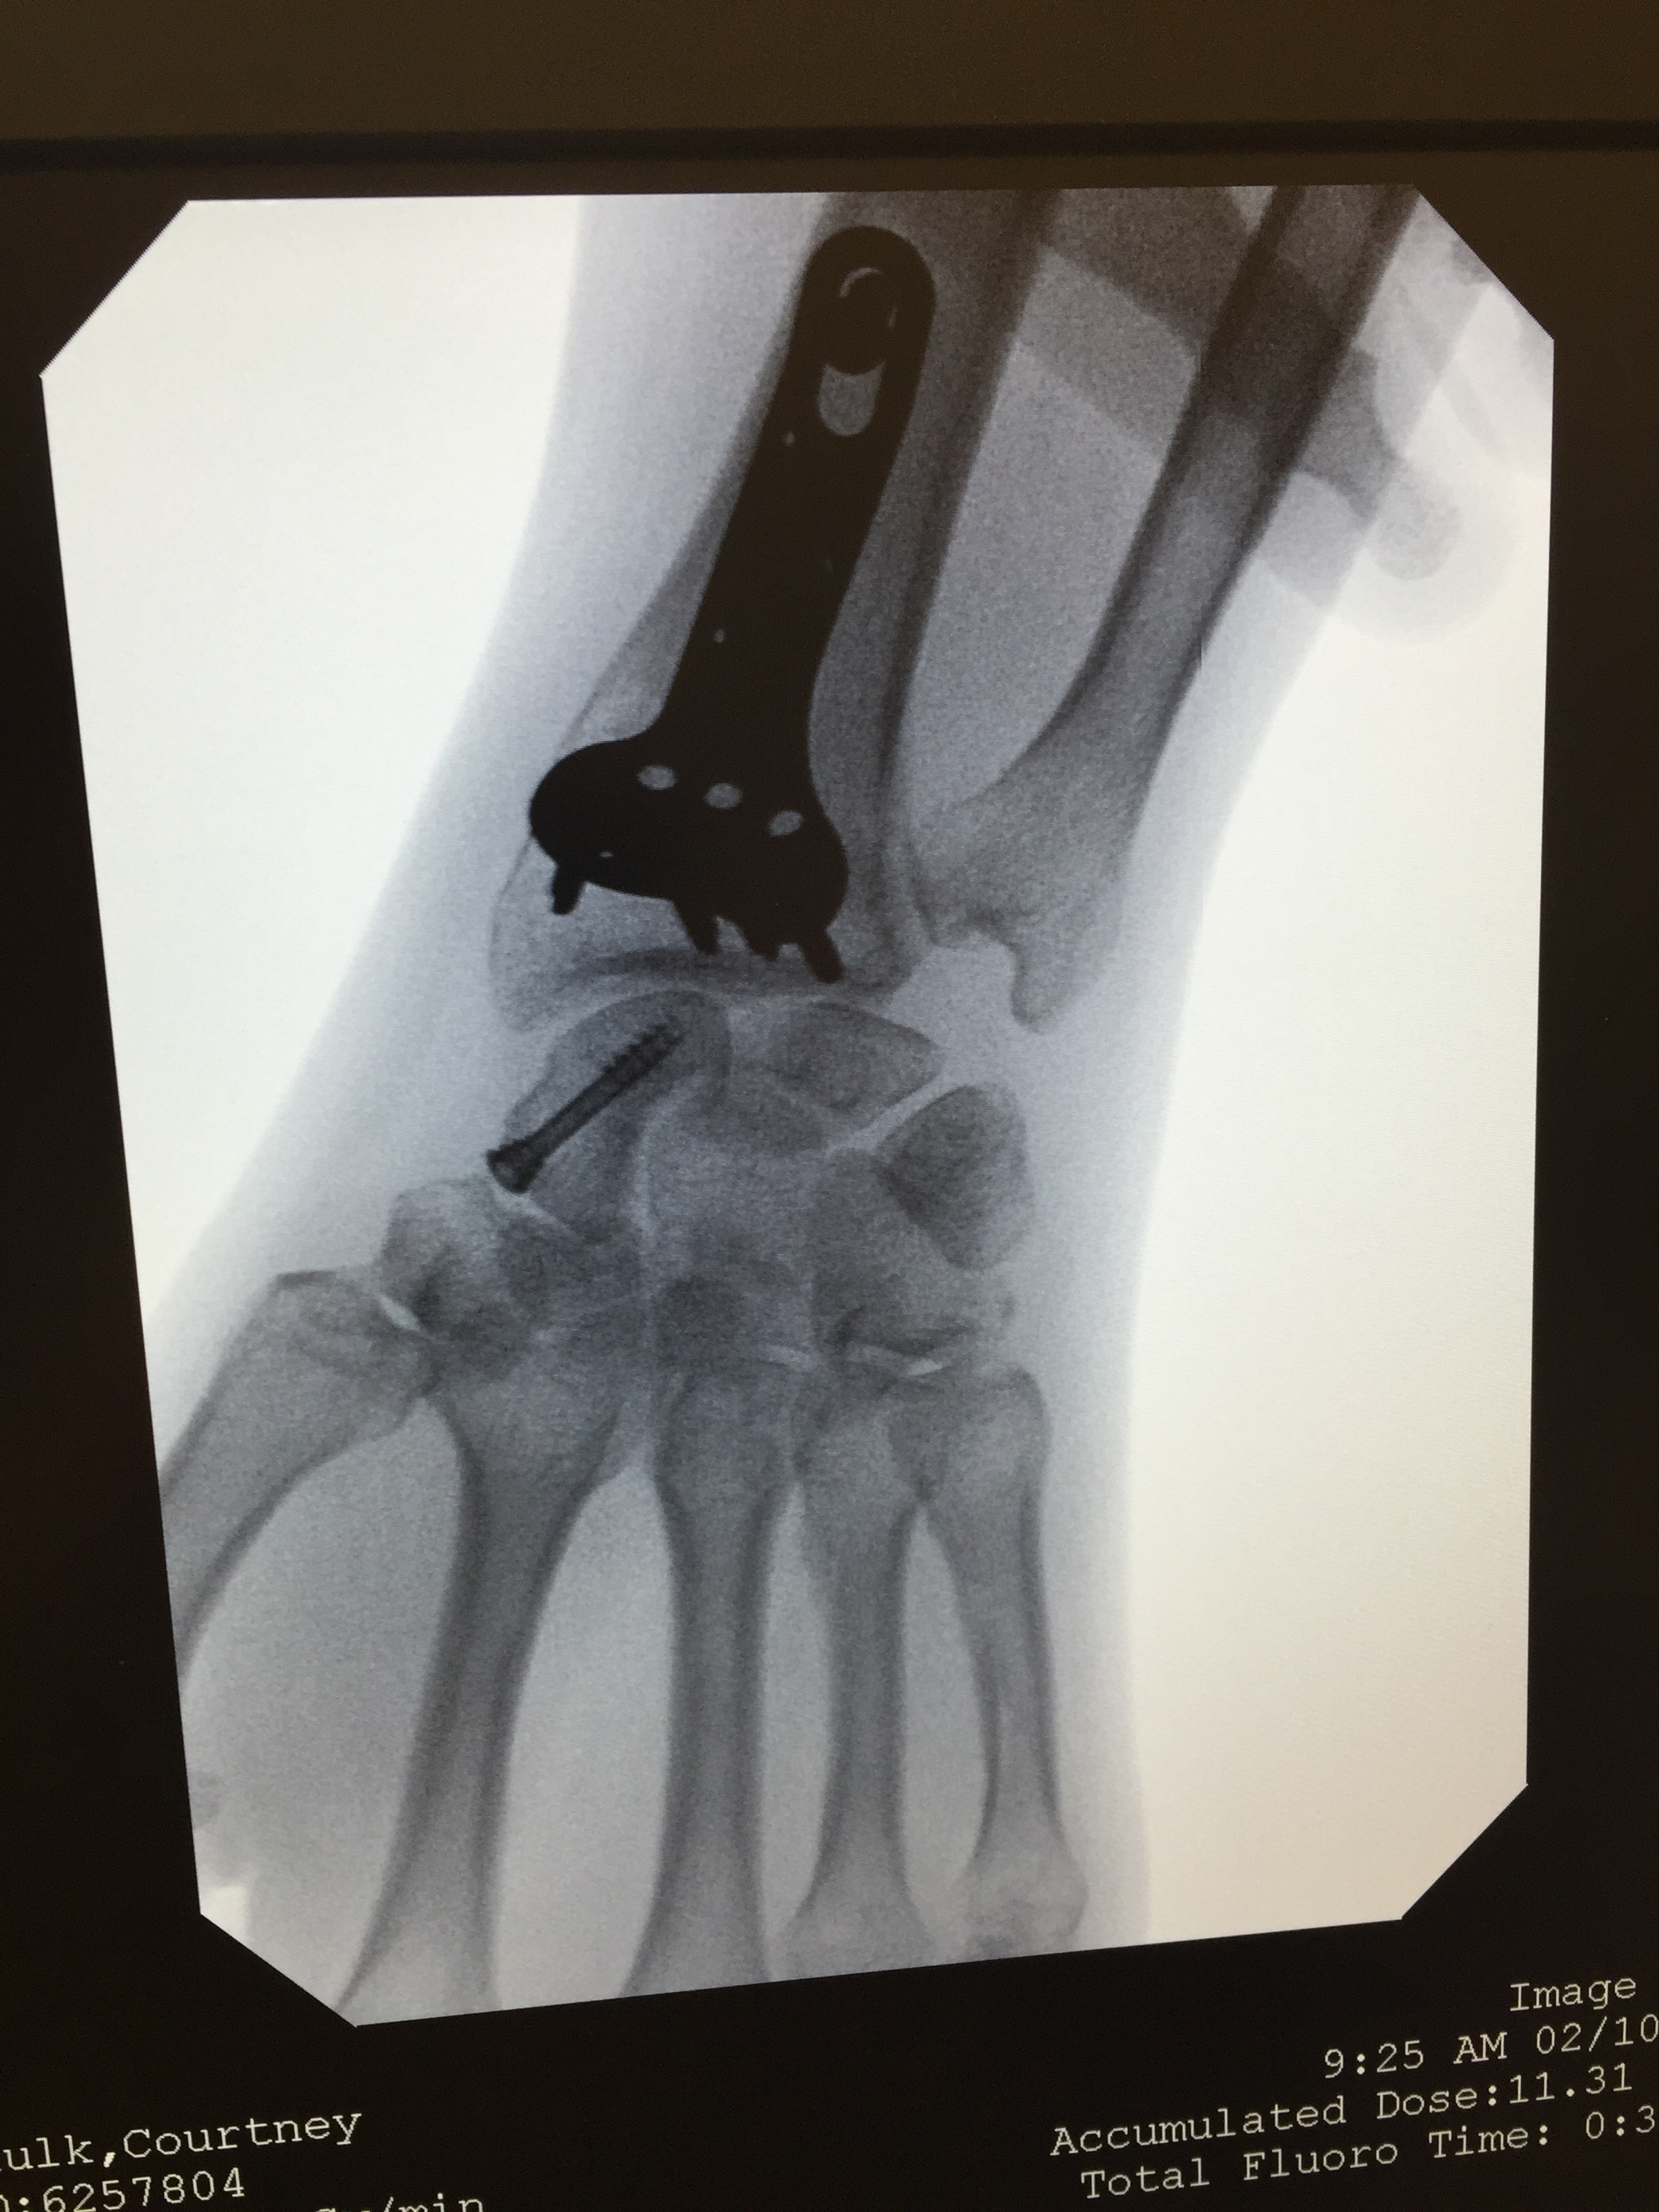

As many of you know, late last November, I broke my left wrist in four places as well as the scaphoid bone in my left hand. The break was bad and I had surgery two days later to have a metal plate and screws put into my wrist and a pin put into my scaphoid. And, so began my journey of recovery.